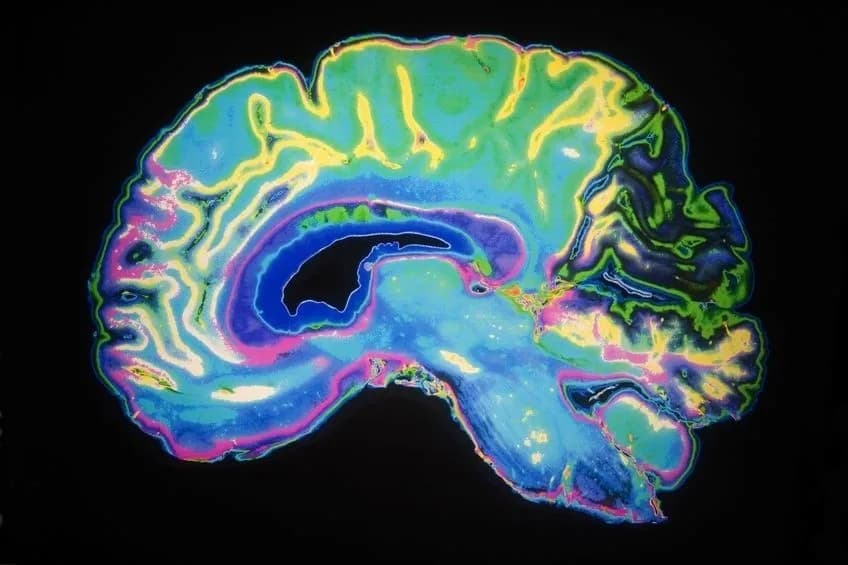

Współczesne metody diagnostyczne, takie jak rezonans magnetyczny (MRI) i tomografia komputerowa (CT), odgrywają ważną rolę w identyfikacji glejaków. Te badania pozwalają na precyzyjne określenie lokalizacji, wielkości oraz rodzaju guza, co jest istotne dla planowania dalszego leczenia.